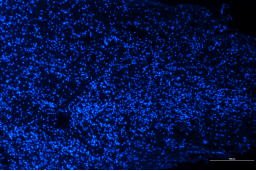

正常對(duì)照組 模型組

脊髓損傷模型GFAP表達(dá)差異對(duì)比

免疫熒光技術(shù)是將免疫學(xué)方法(抗原抗體特異結(jié)合)與熒光標(biāo)記技術(shù)結(jié)合起來研究特異蛋白抗原在細(xì)胞內(nèi)分布的方法。由于熒光素所發(fā)的熒光可在熒光顯微鏡下檢出,從而可對(duì)抗原進(jìn)行細(xì)胞定位,并且可以通過熒光強(qiáng)度對(duì)檢測蛋白的表達(dá)量進(jìn)行半定量分析。